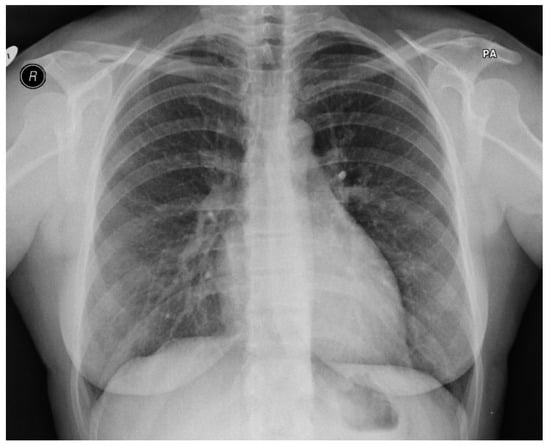

Figure 2.

PA chest X-ray taken on initial admission. Lungs were found to be clear with no focal abnormality identified. The heart and mediastinum were reported as normal.